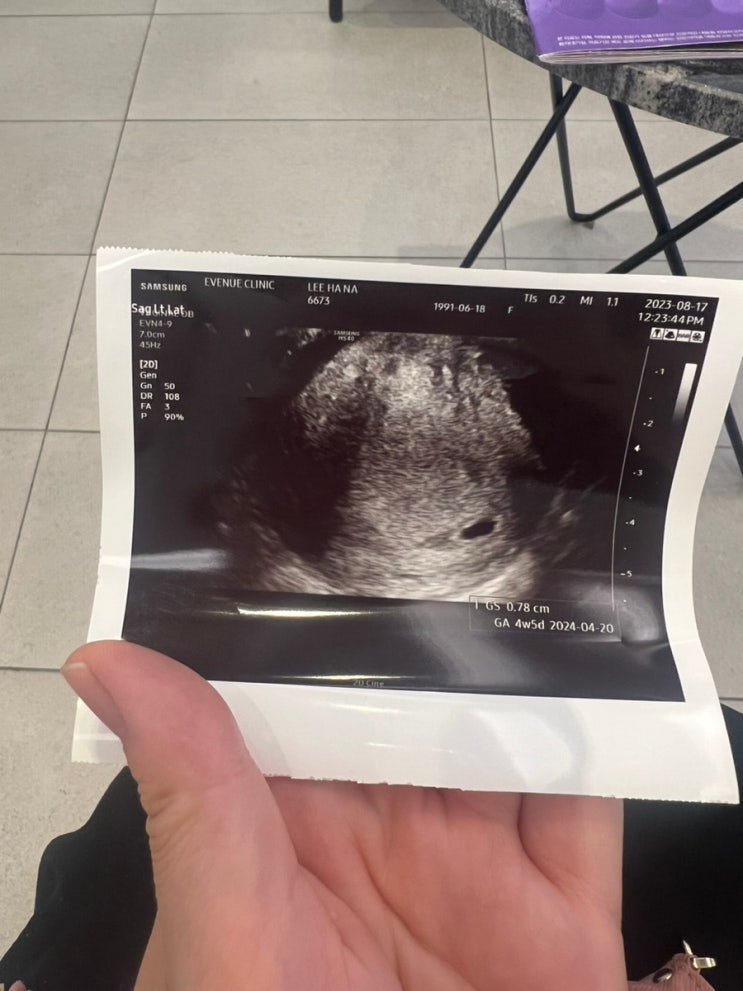

임신 4주차 초음파 , 아기집보다

오늘 네이버 예정일 주수차는 5주3일차라 아기집이라도 보러 가보자는 마음으로 볼일보다 중간에 처음가는 ...

계류유산/고사난자 유산 임신6주차(초음파상 4주5일)난황안보임 아기집

막생 7월10일 시작 네이버 캘린더상 임신주차현재 (6주3일) 8월9일 임신피검사 임신확인 8월17일 초음파 아...

유산일기) 고사난자 7주차 자연배출 소파술안함 자연유산, 바우처사용 용한의원 산후보약

8월 2일 테스트기 두 줄 확인 8월 9일 피검사 임신확인 8월 17일 아기집 확인 8월 24일 아기집 크기 변화 ...